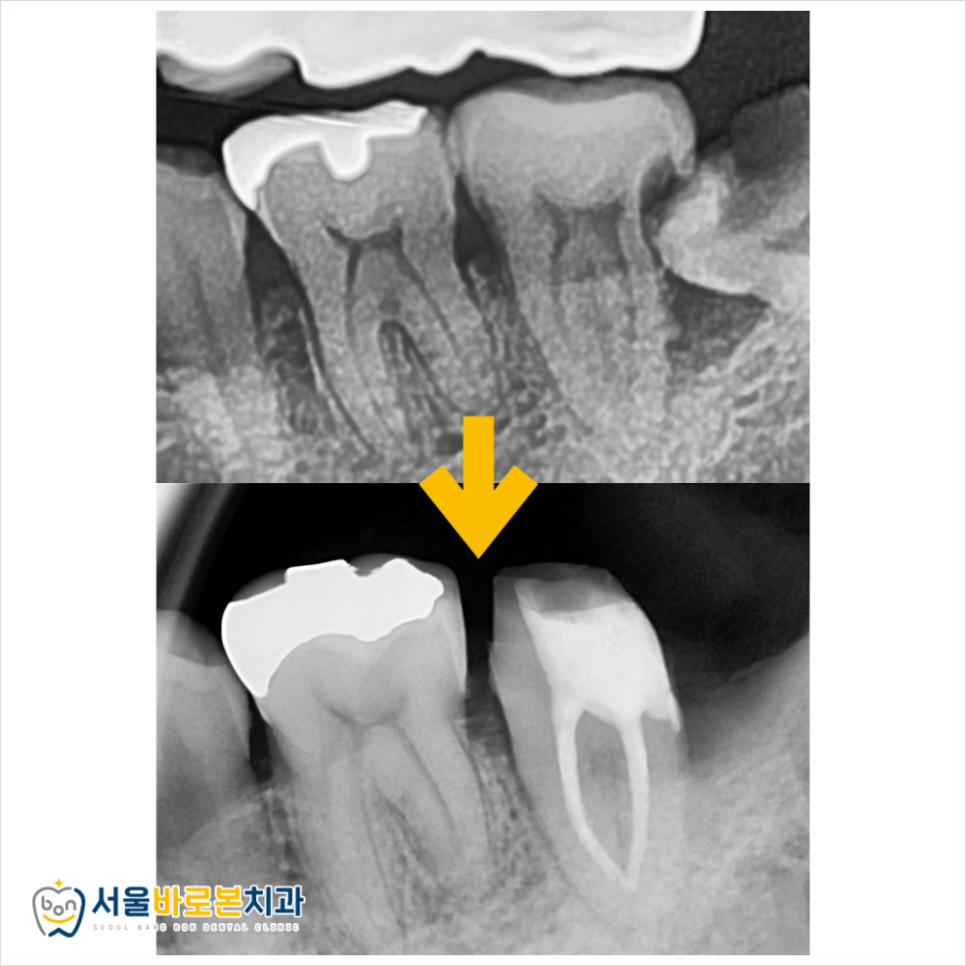

엑스레이 사진은 치아가 썩은 충치 부분을

투과할 수 있어 까맣게 나타나는데요.

구강 내 사진에서는 잘 눈에 띄지 않지만

이렇게 방사선 사진을 촬영해 보면

더욱 발견하이 용이하답니다.

엑스레이 사진에 표시한 부분들이 충치인데,

오른쪽 아래 두번째 어금니

왼쪽 아래 두번째 어금니

왼쪽 아래 사랑니

이렇게 3개의 치아에 심각한 충치를

발견할 수 있었습니다.

사랑니와 더불어 두 번째 큰 어금니들 모두

발치 가능성이 아주 높아 보였고,

다른 치과에서는 발치가 필요하다는

설명도 들으신 상태였는데요.

하지만 서울바로본치과에서는

사랑니만 발치를 하고

2개의 어금니들은 신경치료를 통해

치아를 살려보기로 하였습니다!